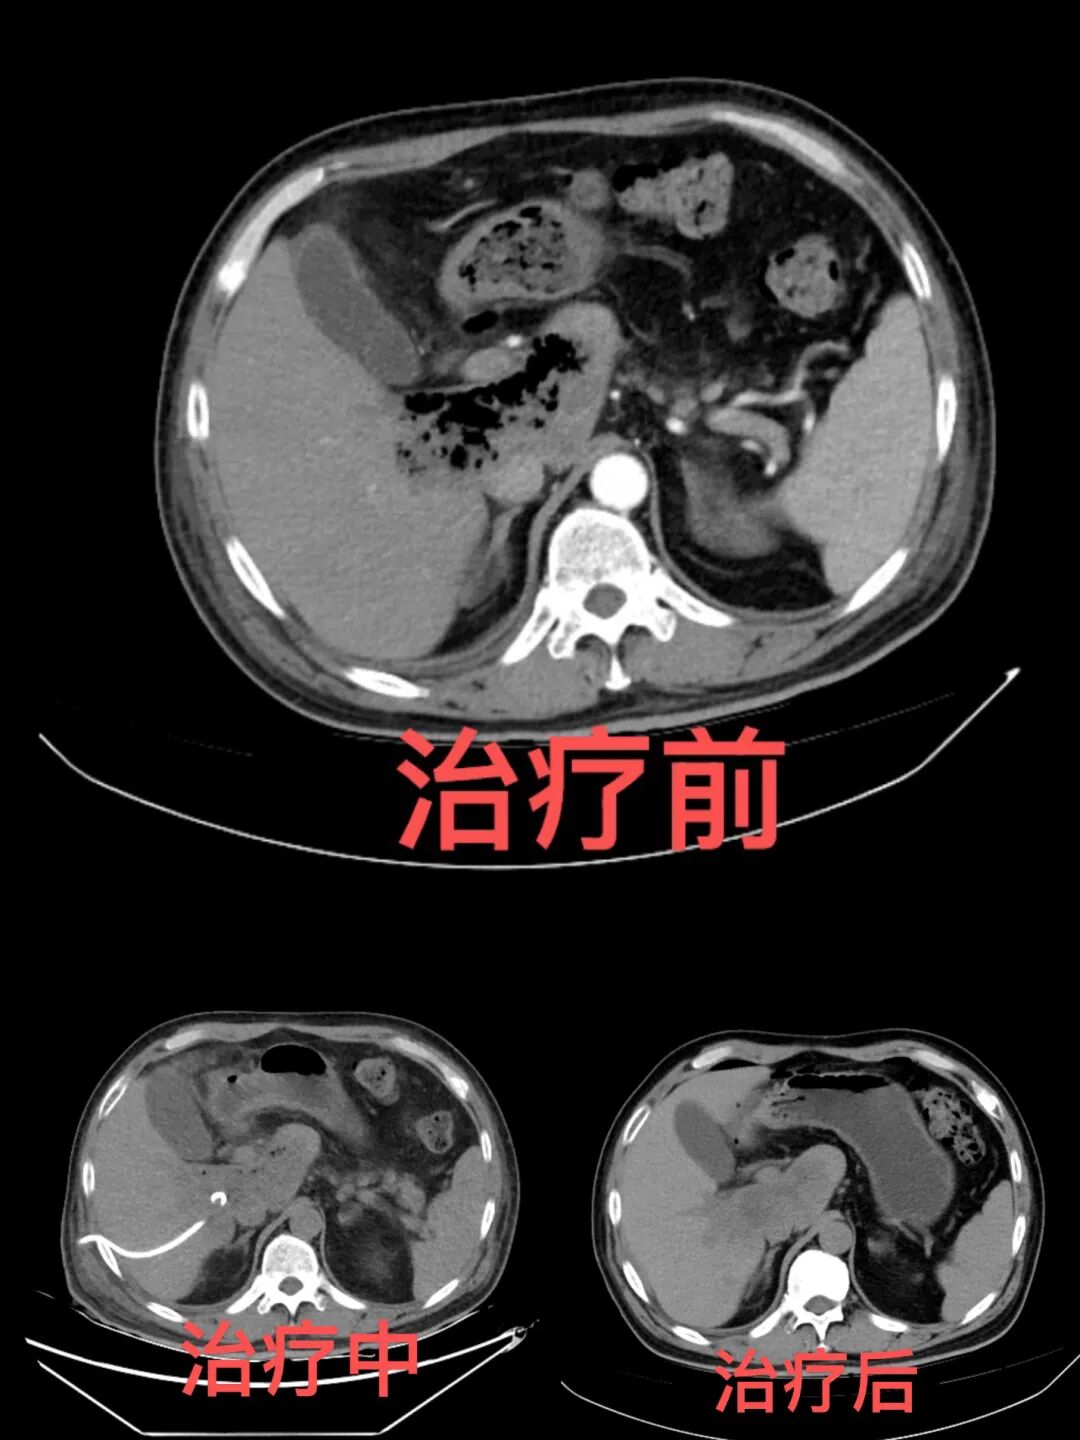

【医疗动态】我院成功救治罕见危重型气肿型肝炎患者

近日,我院感染性疾病科联合超声医学介入室,成功救治一例临床罕见的危重型气肿型肝炎患者,凭借快速的病情识别、精准的诊疗方案和高效的多学科协作,从死神手中夺回患者生命,彰显了我院在疑难危重症救治领域的过硬实力,为该类罕见疾病的临床救治积累了宝贵经验。

患者入院时病情危重、全身状况极差,多系统功能受累,随时可能发生多器官功能衰竭,生命垂危。我院感染性疾病科立即启动急危重症救治预案,快速评估明确诊断后,牵头联合外科、内科、影像科、超声介入、临床药学等科室组建 MDT 团队紧急会诊,精准研判并制定个体化方案,实施精准抗感染、微创介入、生命支持及营养支持等综合治疗。医护团队 24 小时监护,动态调整方案,各项干预措施有序落实。经精心救治与护理,患者病情持续好转,指标恢复、生命体征平稳,恢复自主生活能力,顺利出院。。